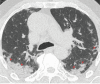

A new type of coronavirus (2019-nCoV) is rapidly spreading worldwide and causes pneumonia, respiratory distress, thromboembolic events, and death. Chest computed tomography (CT) plays an essential role in the diagnosis of viral pneumonia, monitoring disease progression, determination of disease severity, and evaluating therapeutic efficacy. Chest CT can show important clues of 2019-nCoV disease (also known as COVID-19) in patients with an appropriate clinic. Prompt diagnosis of COVID-19 is essential to prevent disease transmission and provides close clinical observation of patients with clinically severe disease. Therefore, radiologists and clinicians should be familiar with the CT imaging findings of COVID-19 pneumonia. Herein, we aimed to review the imaging findings of COVID-19 pneumonia and examine the critical points to be considered for imaging in cases with COVID-19 suspicion.